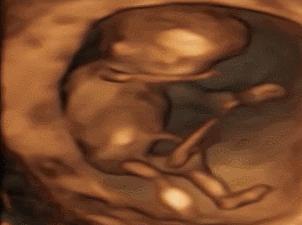

其实小家伙很小的时候就已经开始“闹腾”了:妥妥的一个运动健将!

小碎步向前缩,撅着小屁股用力一蹬,身体向后滑去——“母胎版蛙泳”动作很标准嘛!

▼